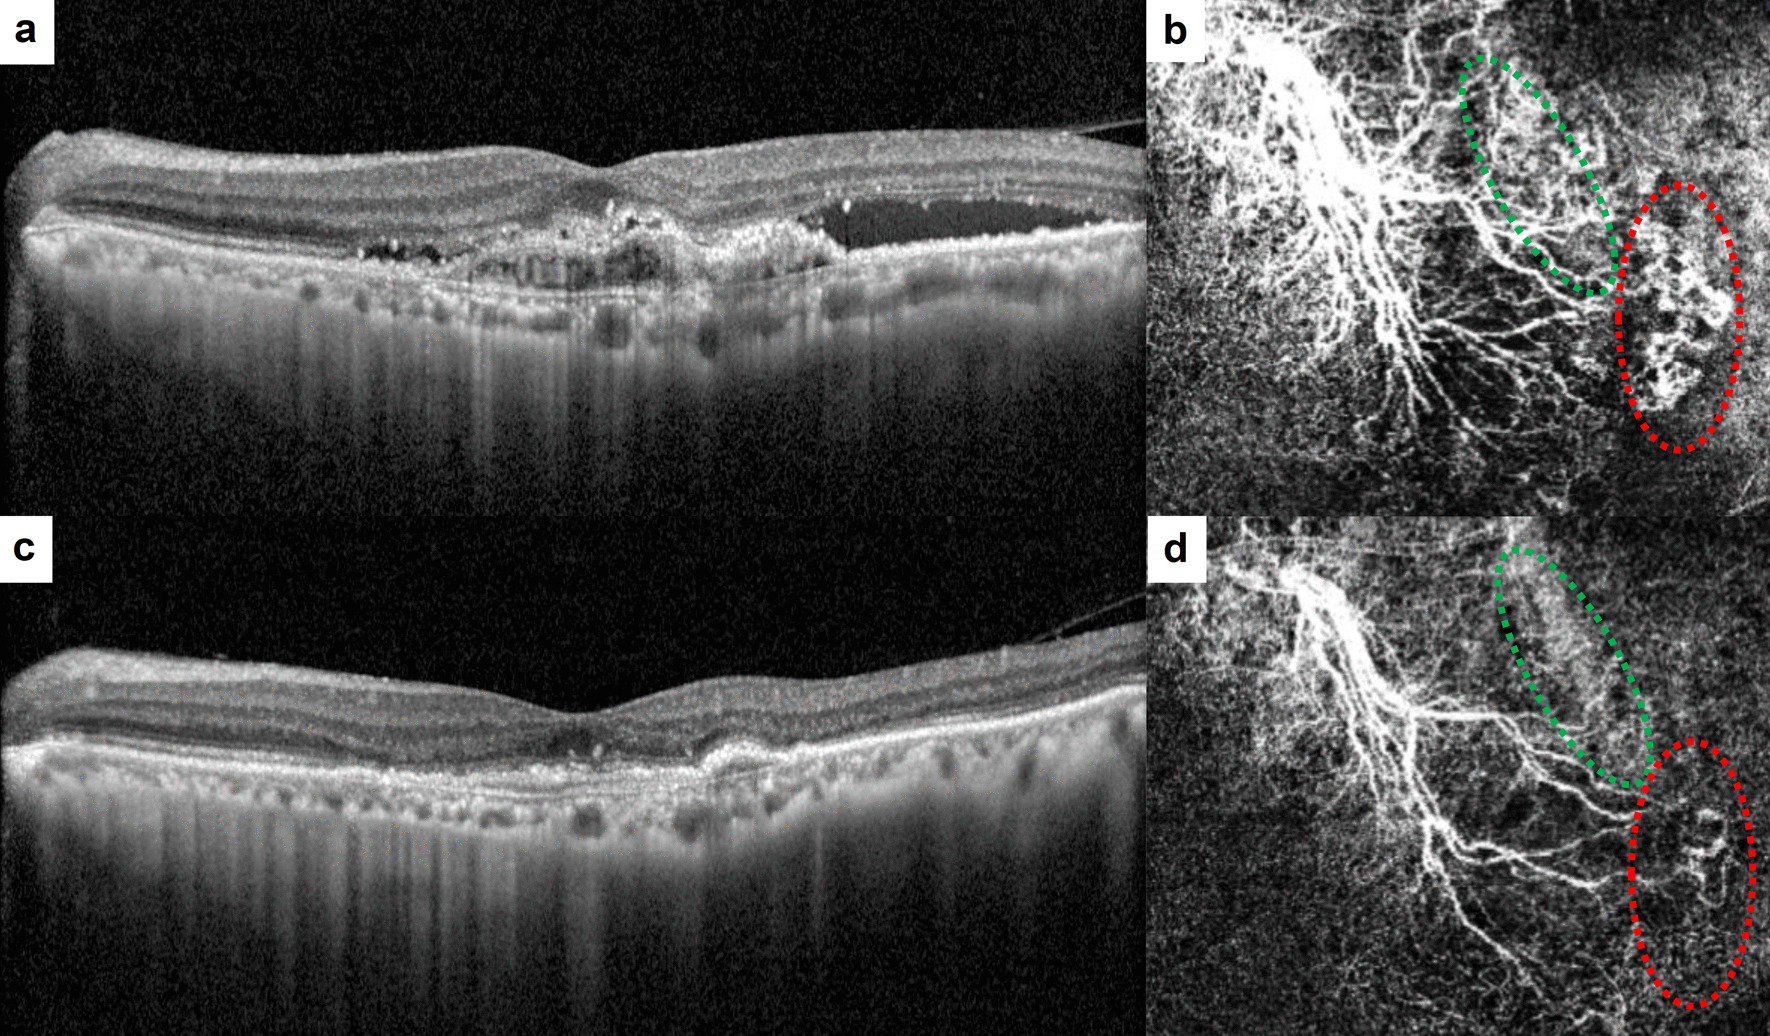

Background: To identify the macular neovascularization (MNV) features in exudative age-related macular degeneration (AMD) patients who exhibited residual fluid after receiving three loading doses of aflibercept.

Methods: Patients were classified into two groups: Group 1, which did not exhibit intraretinal fluid (IRF) and subretinal fluid (SRF), and Group 2, which did exhibit IRF and/or SRF. Optical coherence tomography angiography (OCTA) features were assessed and compared between the groups.

Results: A total of 101 eyes were enrolled; 65 for Group 1 and 36 for Group 2. No significant differences were found in baseline MNV size (2.94 ± 2.51 µm2 vs. 2.22 ± 2.26 µm2, P = 0.178) or vessel density (47.1 ± 15.4 % vs. 41.3 ± 10.5%, P = 0.052) between Groups 1 and 2. There were significant differences in the presence of loops (52.3% vs. 75%, P = 0.026) and peripheral arcades (29.2% vs. 55.6%, P < 0.001) at baseline between the two groups. In Group 1, there was a significant reduction in the presence of branching (P < 0.001) and loops (P = 0.016) after treatment. In Group 2, only the presence of branching decreased significantly (P < 0.001) after treatment. Multivariable analysis revealed that the presence of a peripheral arcade (B = 4.77, P = 0.001) was significantly associated with residual fluid.

Conclusions: Although responding to treatment, the presence of loops and peripheral arcades in exudative AMD patients may contribute to residual fluid following the three loading doses of aflibercept. The peripheral arcade, in particular, may play a more significant role in the presence of residual fluid.